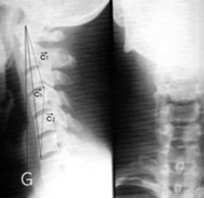

거북목이 발생하면 경추의 만곡이 없어지면서 머리가 인체 중심 중력선보다 앞으로 튀어 나오게 됩니다.

이렇게 되면 보상이 일어나 상체는 뒤로 물러나고 골반은 전방으로 경사되면서 ‘새로운’ 그러나 적절하지 않은 배열이 구조적으로 불안정한 환경으로 발전되고 신경계 기능도 감소합니다.

여러가지 체형변화가 일어나지만 거의 대부분 공통적으로 거북목 현상이 일어납니다. 거북목이란 몸통에 비해 목이 앞으로 빠져 나오는 현상을 말하는데 위의 그림에서 중심중력선이 귀를 지나가야 하지만 비정상적인 체형시에는 중심중력선이 귀를 통과하지 못함을 볼 수 있습니다.

일자화가 되면 중심 증력선이 균형이 무너지게 되어 척추 중심중력선이 정상적인 것보다 앞에 위치하거나 뒤에 위치하게 되는데

위의 그림처럼 앞에 위치하게 되면 척추체의 후면인 섬유륜 부위에 열상이 생긴 경우 음압을 형성하여 탈출의 조건을 형성하게 됩니다.